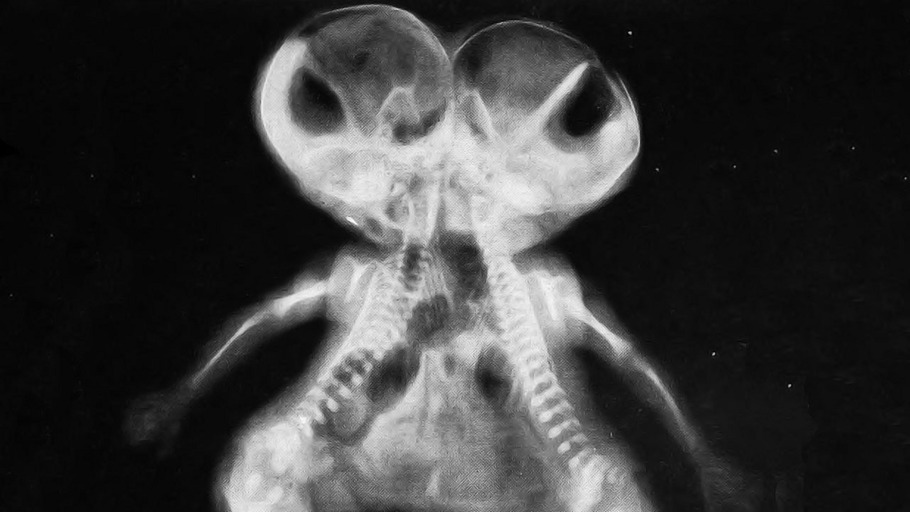

Eineiige Zwillinge bilden eine besondere Menschengattung. Unter ihnen sind die siamesischen Zwillinge nochmals eine besondere Art. Zwei Körper bilden einen Menschen.

Wie man aus Singapur weiß, kann die Trennung siamesischer Zwillinge für beide Teile tödlich enden. Die Natur kennt viele zusammengesetzte Lebewesen.